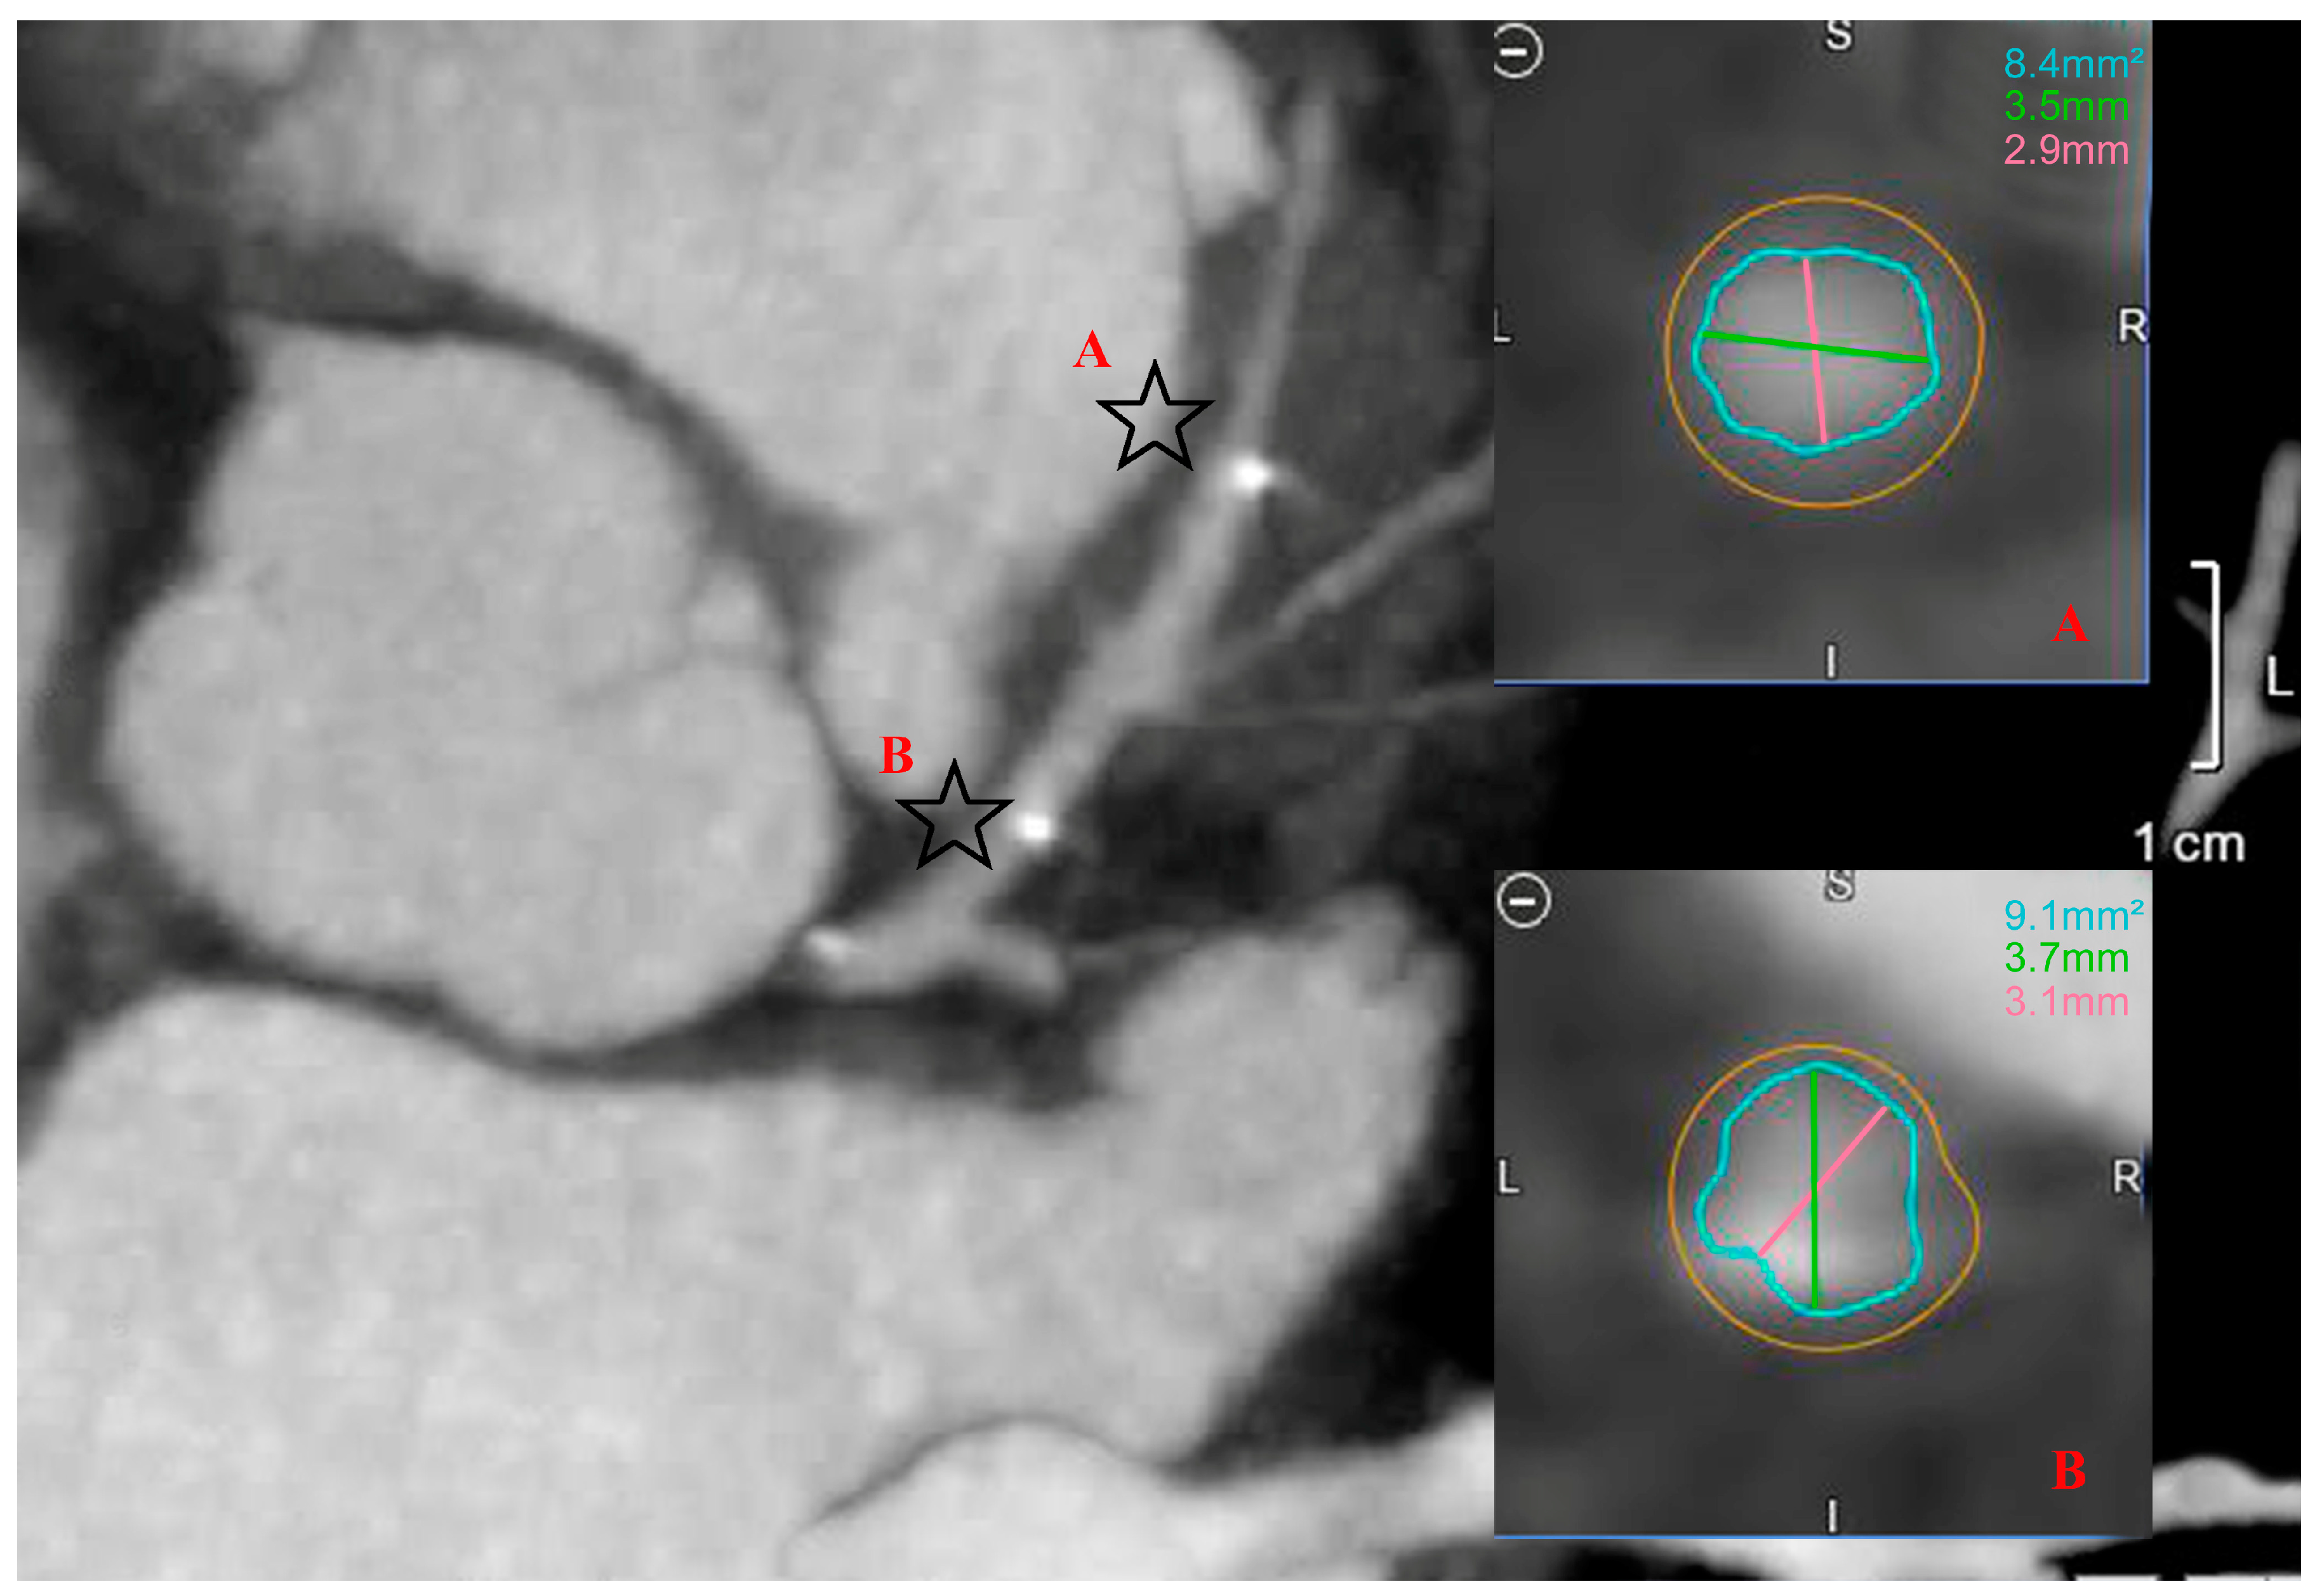

| n | 15 | 17 | 32 | |

| Date difference (months) | 7.1 ± 4.5 | 5.6 ± 2.5 | 6.4 ± 3.7 | NS |

| Proximal vessel diameter (mm) | 4.0 ± 0.3 | 3.8 ± 0.7 | 3.9 ± 0.5 | NS |

| Distal vessel diameter (mm) | 3.3 ± 0.6 | 3.1 ± 0.6 | 3.2 ± 0.6 | NS |

| Proximal surface area (mm2) | 9.4 ± 1.9 | 10.0 ± 3.7 | 9.7 ± 2.9 | NS |

| Distal surface area (mm2) | 7.4 ± 2.1 | 7.1 ± 2.9 | 7.2 ± 2.5 | NS |

| In-stent minimal diameter (mm) | 2.4 ± 0.4 | 2.4 ± 0.7 | 2.4 ± 0.6 | NS |

| In-stent maximal diameter (mm) | 4.1 ± 0.5 | 3.9 ± 0.9 | 4.0 ± 0.8 | NS |

| Minimal in-stent surface area (MSA) (mm2) | 6.1 ± 1.2 | 6.8 ± 2.6 | 6.5 ± 2.0 | NS |

| Maximal in-stent surface area (mm2) | 11.3 ± 2.5 | 10.9 ± 3.4 | 11.1 ± 3.0 | NS |

| Mean proximal to distal surface area (mm2) | 8.4 ± 1.6 | 8.5 ± 2.9 | 8.4 ± 2.3 | NS |